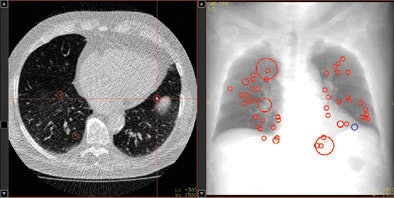

| Above, axial CT image in standard-dose CT (SD-CT) showing a nodule in juxtadiaphragmatic location missed by CAD-1. Above right, CAD markers resulting from the analysis of the SD-CT data presented in a coronal view. Below, CAD analysis of the ultralow-dose CT (ULD-CT) data resulted in automated detection of the corresponding nodule in the left lower lobe. On the right, CAD markers resulting from the analysis of the ULD-CT data. All images courtesy of Dr. Valentina Romano. |

Median false-positive rates per patient were five for CAD-1 versus six for CAD-2 with SD-CT. For ULD-CT, rates were eight for CAD-1 and three for CAD-2.

After separate statistical analysis of nodules with diameters of 5 mm and larger, detection rates increased to 83% for CAD-1 and 61% for CAD-2 at SD-CT and to 89% for CAD-1 and 67% for CAD-2 at ULD-CT. Overall, for both CAD systems, there were no significant differences between the detection rates for standard-dose and ultralow-dose datasets (p > 0.05).

Still, the number of false positives was highly variable by case, CAD system, and the use of standard or low-dose CT protocols.

"In case 21, CAD-1 found more than 25 false-positive nodules in a standard-dose CT scan," Romano said. "If we look at the ultra-low-dose results for CAD-2 [in the same case], there were absolutely no false-positive findings. In another example, there were more than 35 false-positive findings in CAD-1 in the ultra-low-dose dataset and only five false positives using standard dose for both CAD systems."

Differences between the systems could also be seen in the distribution of detected nodules, she said. "CAD-1 seemed to have more difficulties finding nodules close to the vessels, with 56% of the nodules missed," she said. CAD-2 had more difficulty finding nodules close to the pleural surface, with 42% missed nodules.